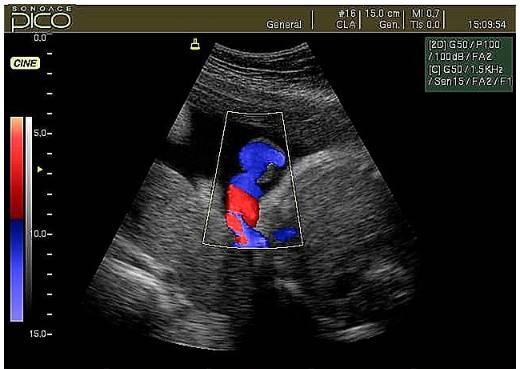

- Режим дуплексного сканирования. С его помощью производят оценку кровеносных сосудов плода, матки и плаценты. Изображение появляется на экране в черно-белом варианте. Режим также используют для замера скорости кровотока.

- Режим триплексного сканирования отличается большей точностью. Во время процедуры на экране появляется изображение в цвете, видно, как протекает кровообращение и в артериях, и венах. Но цвет зависит только от направления кровотока.

Беременным предпочтительнее делать триплексное сканирование, так как оно позволяет делать фиксацию движения кровяных телец и знать их количество. Результаты доплера при беременности очень важны, так как при каких-либо отклонениях от нормы врач определяет причины, по которым произошло отклонение и назначает лечение.